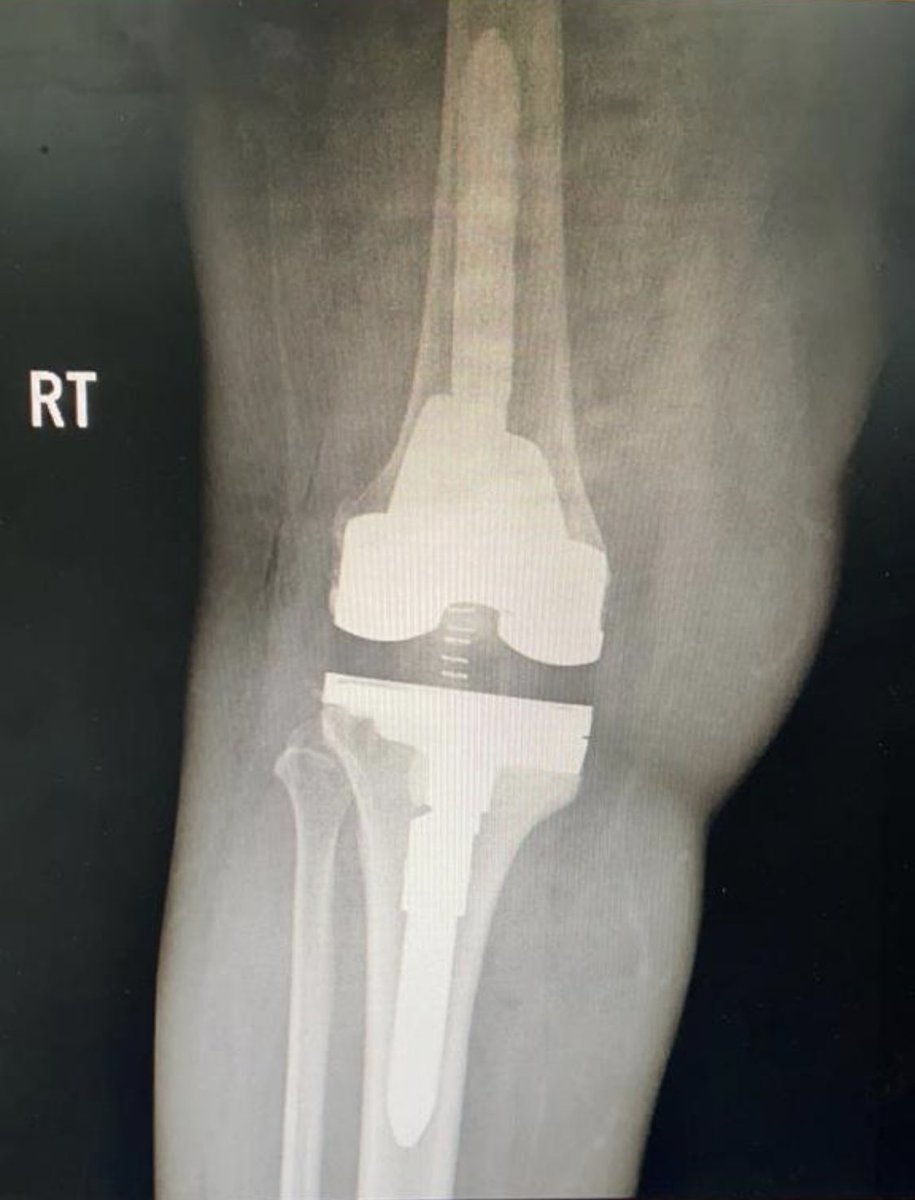

وان اهم واحد من هذه الحلول هي عمليات تلبيس او استبدال المفصل

التاخر في قرارها ينتج بتحول هذه العملية من بسيطة وروتينية الى معقدة تستنزف الجهد والمال سواء لمقدم الخدمة الصحية او شركة التامين او حتى المريض